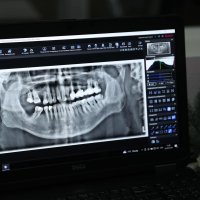

- рентгенівський дентальний апарат;

«Тепер військові можуть отримати панорамні рентген-знімки безпосередньо у закладі. Знімки автоматично передаються лікуючому лікарю через єдину мережу. Це значно зменшує витрати часу – усе необхідне обстеження та лікування проходить в одному місці, без додаткових відвідувань інших клінік. Це дуже зручно і для тих, хто перебуває у стаціонарі». – зауважила Наталя Заболотна.